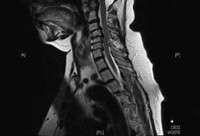

Doença degenerativa da coluna cervical

Ressonância nuclear magnética (RNM) cervical (T2 sagital) com doença articular degenerativa moderada, mas sem compressão significativa da medula espinhal

Dennis A. Turner, MA, MD